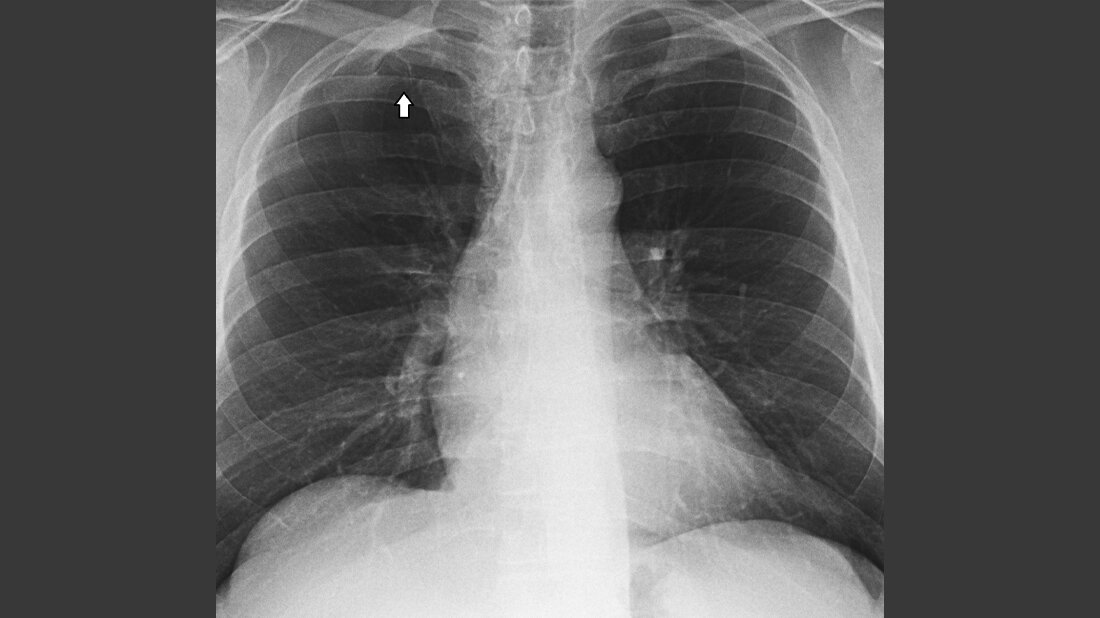

Normalvarianten sind klinisch ohne Bedeutung. Sie können bei der klinischen Untersuchung palpabel sein oder bei Röntgenaufnahmen des Thorax gefunden werden. Die Varianten können sich mit zahlenmäßigen Veränderungen, Lokalisation, Mineralisation und Konturveränderungen darstellen. Knochenbrücken zwischen den Rippen werden als normale Varianten gefunden, bekannt als Srb’sche Anomalie. Rippenanomalien, die mit einer Minderzahl und Unterentwicklung der oberen Rippen einhergehen, können zu verschiedenen Beschwerden führen.

Normal variants are usually clinically insignificant; they are occasionally palpated at clinical examination or detected incidentally at chest radiography. Signs of abnormality can appear in the ribs as variations in number, size, mineralization, and shape. Bony bridges of the ribs can be seen as a normal variant. This is known as Srb anomaly. Rib anomalies, consisting in a reduction in the number or size of the upper ribs can be associated with symptoms.